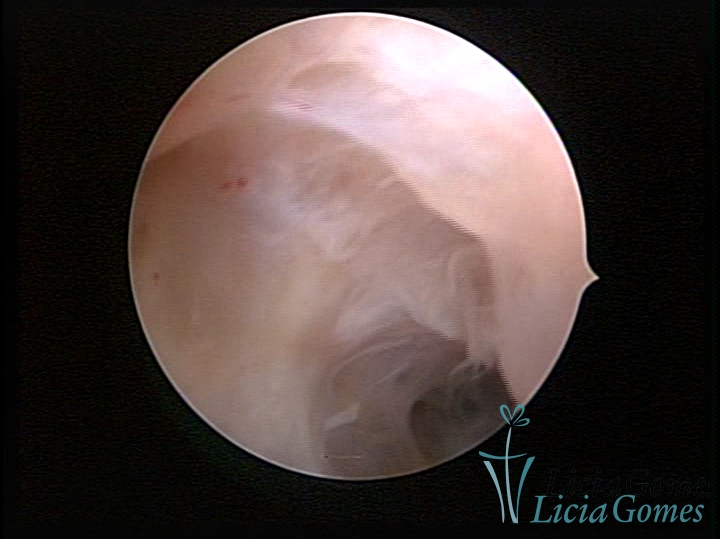

• SINÉQUIA TIPO FIBROSA